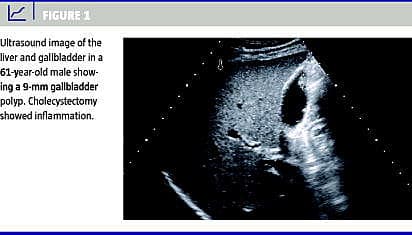

Galdeblærepolypper (GP) er et hyppigt, tilfældigt og sjældent symptomgivende fund ved abdominale ultralydskanninger (US) og findes i stigende grad med den tiltagende brug af US. Patienter med GP større end 10 mm eller størrelsestilvækst i GP bliver typisk henvist til kolecystektomi pga. den øgede risiko for malignitet. Ved små GP på mindre end 10 mm bliver patienten oftest indkaldt til kontrol-US med henblik på tilvækst, men der er ikke enighed om håndteringen af små GP. Formålet med dette studie var at undersøge størrelsesfordelingen af GP og udfaldet af opfølgende US for små GP.